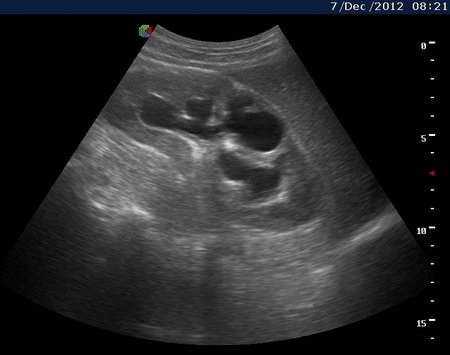

Вот как выглядит почка при первом осмотре и в феврале

Видим длительно существующий гидронефроз вследствие процесса в области лоханочно-мочеточникового сегмента (видео 1), с утолщением стенок ЧЛС и истончением паренхимы почки - наиболее частая причина у взрослых - туберкулез.